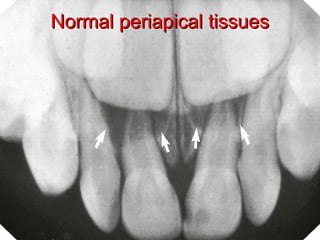

Normal periapical tissuesNormal periapical tissues

 Normal intact lamina duraNormal intact lamina dura

 Normal PDLNormal PDL

Normal periapical tissuesNormalperiapical tissues  No pain al allNo pain al all  Not be abnormally sensitive to percussionNot be abnormally sensitive to percussion or palpation testingor palpation testing  Normal intact lamina duraNormal intact lamina dura  Normal PDLNormal PDL